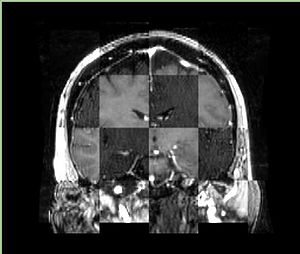

• Checkerboard appearance of unregistered images for the representative data of interest

• Case01